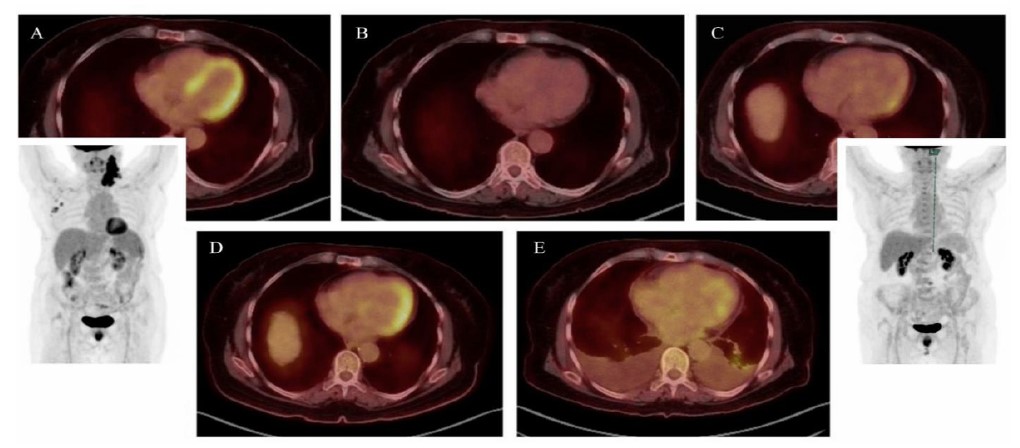

A retrospective case review revealed peaks in acute-phase reactants, eosinophilia, and β2-microglobulinemia prior to chemotherapy, with transient normalization following tumor response and a subsequent rise at the time of cardiac disease onset (Fig. 5). In five consecutive PET-CT scans conducted to monitor her oncologic disease, signs indicating myocardial inflammation were observed, aligning with spikes in laboratory markers (Fig. 6). Taken together with the highly suggestive cardiac CMR findings, these results support a probable diagnosis of paraneoplastic EM known in its thrombotic phase as Loeffler endocarditis, within the context of cHL, and likely worsened by doxorubicin-based chemotherapy.

Sequential PET-CT axial and volumetric reconstructions during patient follow-up, demonstrating: (A) the active phase of Hodgkin’s lymphoma with prominent, widespread myocardial uptake (late 2021); (B) following initial chemotherapy cycles, a complete oncologic response with no myocardial uptake (early 2022); (C) several months after finishing chemotherapy, revealing early signs of myocardial uptake while the patient remained asymptomatic from a cardiovascular perspective (late 2022); (D) the onset of clinical heart failure, exhibiting intense, asymmetric uptake corresponding to areas of increased gadolinium enhancement on CMR (mid 2023); (E) end-stage cardiomyopathy, showing relatively decreased and patchy uptake, consistent with established myocardial fibrosis (mid 2024, two months before the patient’s passing).

Doxorubicin-based chemotherapy, a well-known cardiotoxic agent and a recognized contributor of diffuse endocardial fibrosis (typically with more subtle and patchy involvement that goes beyond the endocardium) [5], may have played a role in the patient's condition. As highlighted by the 2022 ESC guidelines, cancer patients undergoing chemotherapy are likely to benefit from structured monitoring strategies to identify early signs of cardiotoxicity through regular testing [6]. In this case, EM-related metabolic activity observed on sequential PET-CT scans with unprecedented temporal correlation underscores the potential of this imaging modality for both early diagnosis and longitudinal follow-up [7].